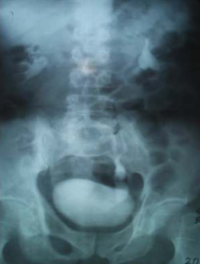

Ureterocele in an Adult Male Nigerian: a Case Report

Ajadi A. Taofeek, Oseni Ismaila, Ogunmoroti O Abel, Onifade A Adekunle (Author)

53-57

PDF